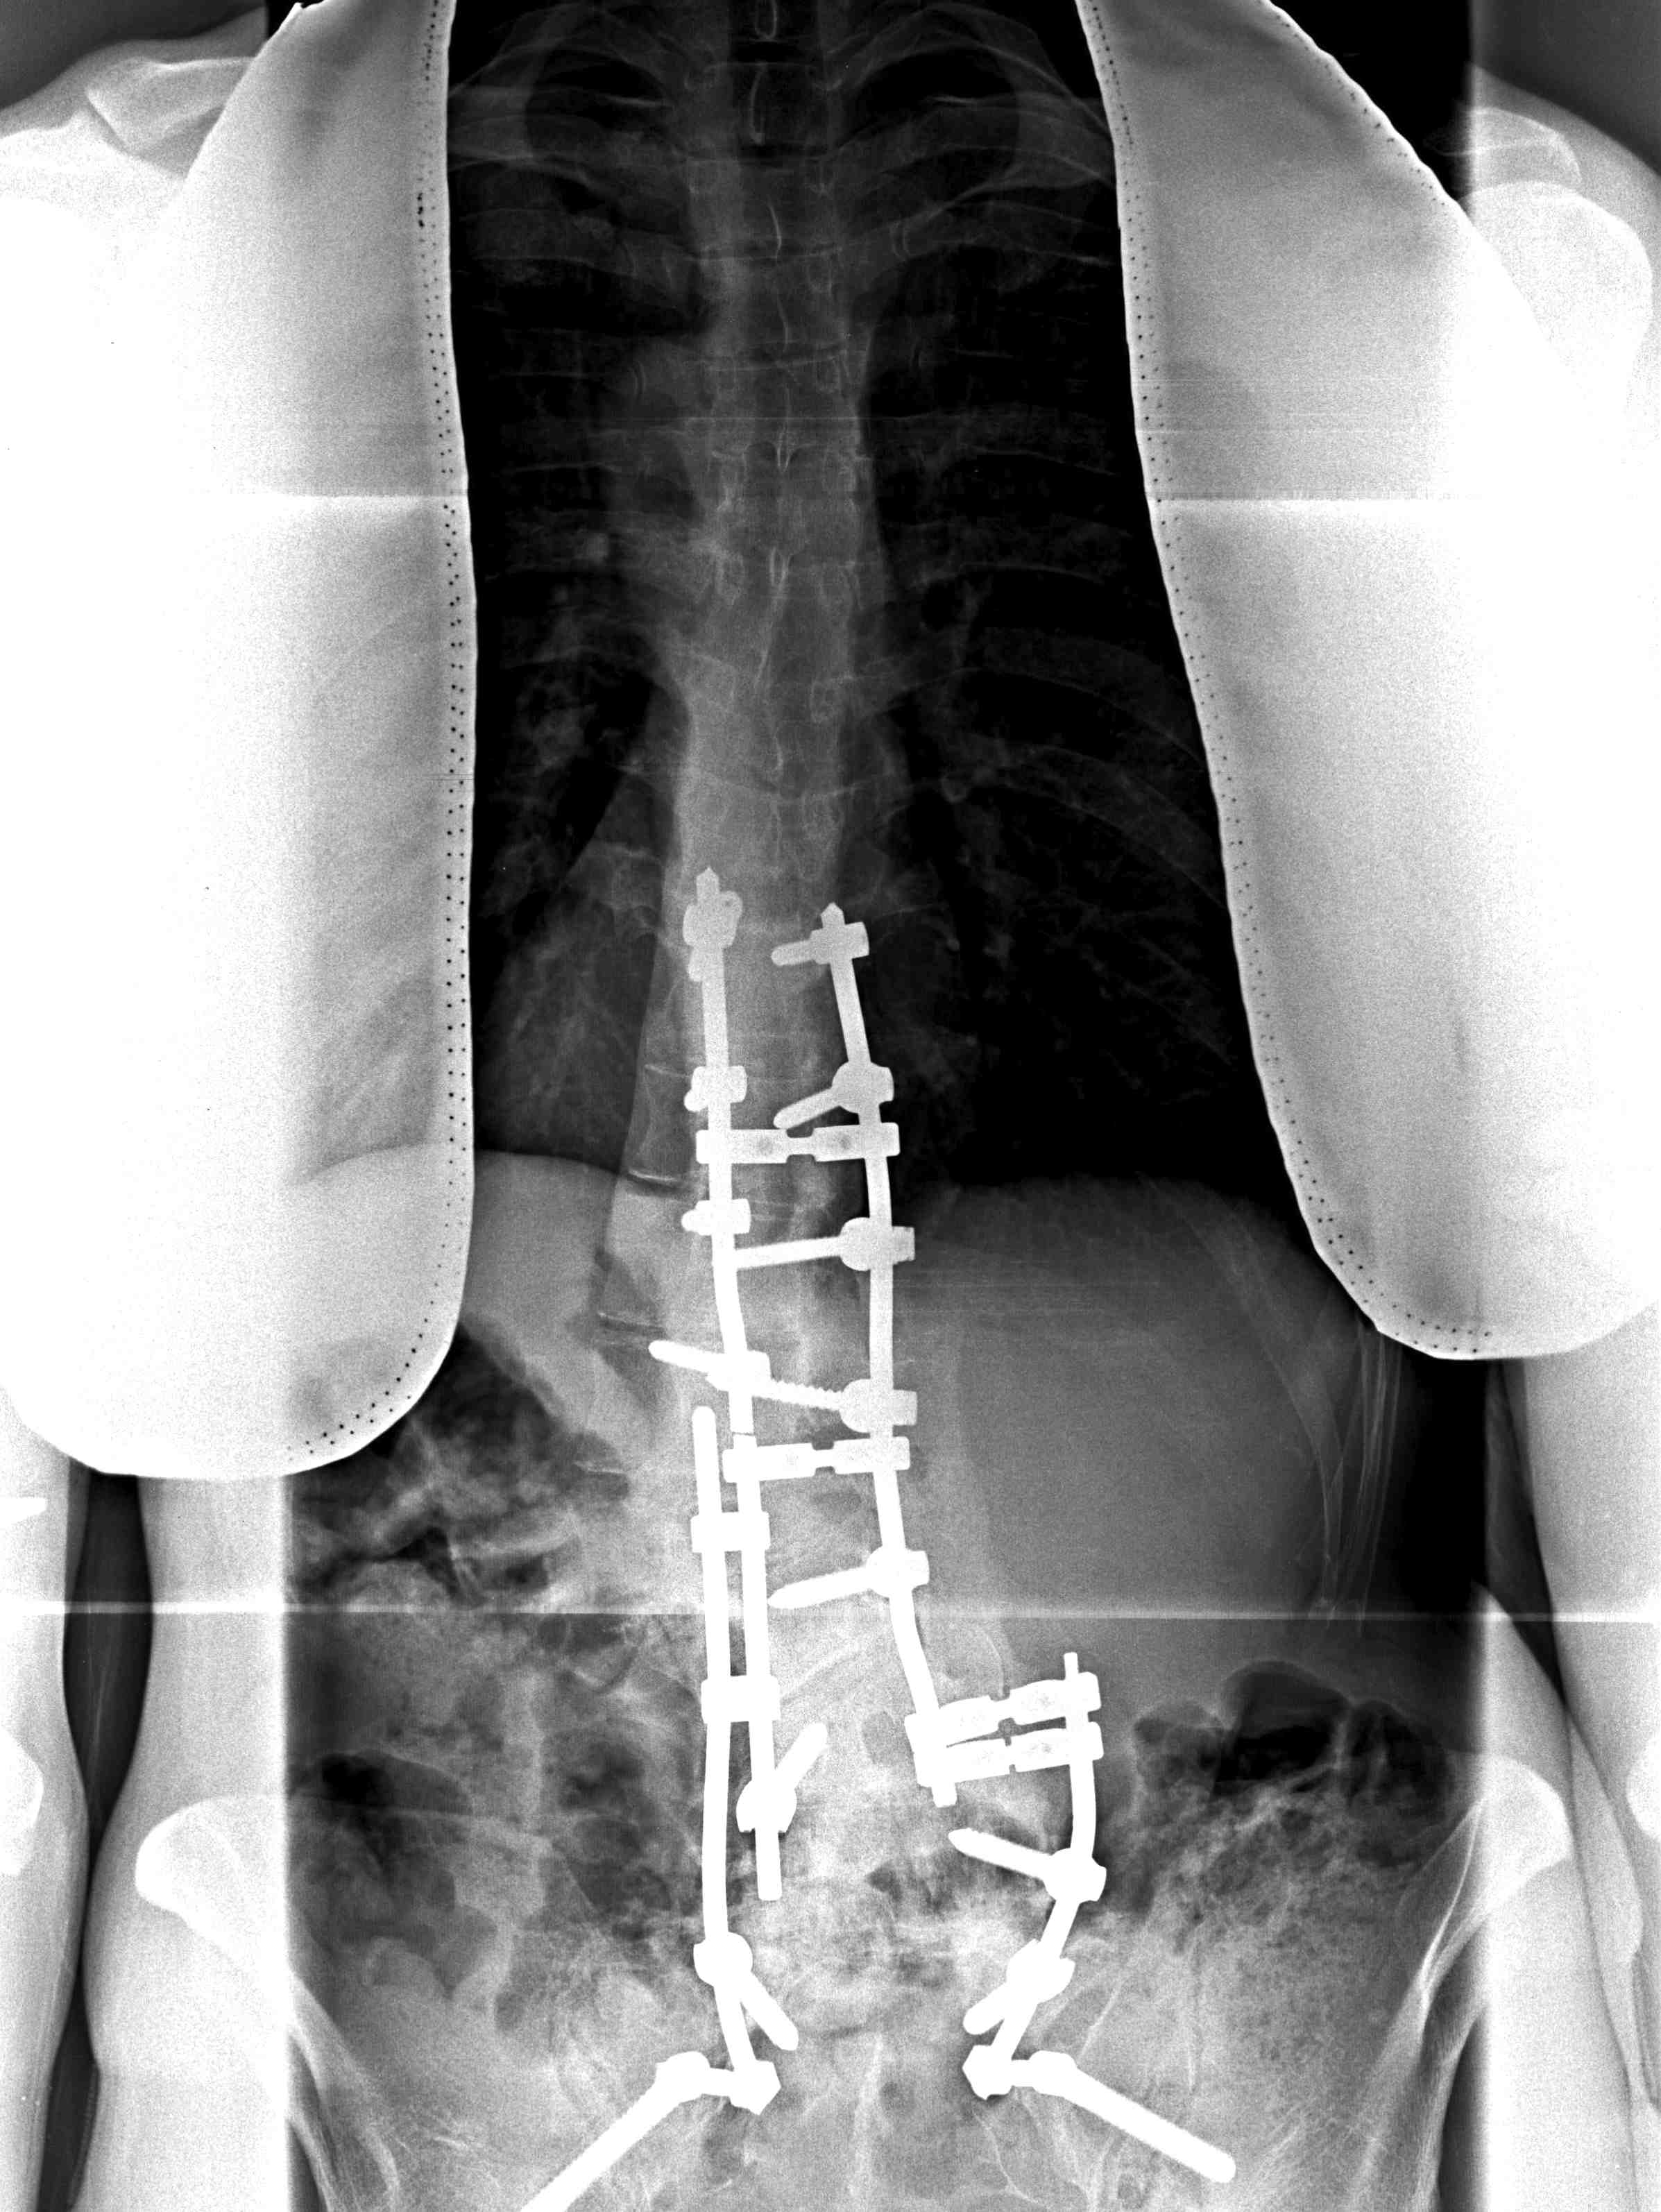

Technique Anterior Fusion

Indications

Large lumbar curve in young patients

- skeletally immature patient to achieve growth arrest and prevent crankshaft

Any lumbar curve to decrease fusion length

- this is debatable

Large / rigid curve to achieve mobility

- severe curves >70o

- supplement posterior fusion

Technique

Supine, rolled

- curved right sided approach

- remove 9th rib (save for bone graft)

- through bed of rib

- identify peritoneum, stay outside

- take down diaphragmatic crura

- divide segmental vessels, remove discs

- unilateral screws and rod

- repair diaphragm, close over ICC